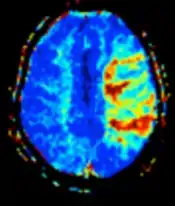

Perfusion weighted (PWI) | Dynamic susceptibility contrast | DSC | Measures changes over time in susceptibility-induced signal loss due to gadolinium contrast injection.[23] |

Perfusion-weighted imaging (PWI) is performed by 3 main techniques:

- Dynamic susceptibility contrast (DSC): Gadolinium contrast is injected, and rapid repeated imaging (generally gradient-echo echo-planar T2 weighted) quantifies susceptibility-induced signal loss.[45]

The acquired data is then postprocessed to obtain perfusion maps with different parameters, such as BV (blood volume), BF (blood flow), MTT (mean transit time) and TTP (time to peak).

In cerebral infarction, the penumbra has decreased perfusion.[24] Another MRI sequence, diffusion-weighted MRI, estimates the amount of tissue that is already necrotic, and the combination of those sequences can therefore be used to estimate the amount of brain tissue that is salvageable by thrombolysis and/or thrombectomy.